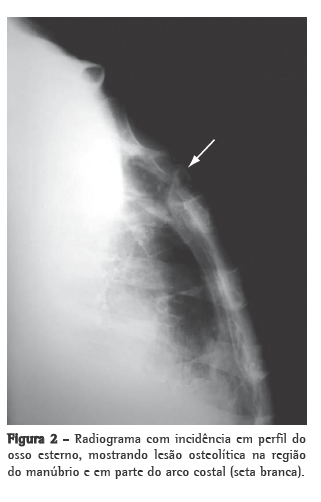

Homem de 74 anos, branco, agricultor aposentado, não-tabagista e ex-etilista, apresenta-se com dor torácica na porção superior do esterno iniciada há um ano com edema e eritema local, agravada há duas semanas com fístula que drenava secreção purulenta. Ainda referia febre vespertina, sudorese noturna e emagrecimento de aproximadamente 25 kg nos últimos 12 meses. O paciente fazia acompanhamento ambulatorial em várias unidades do Hospital Universitário de Santa Maria por apresentar múltiplas comorbidades: hipertensão arterial sistêmica, insuficiência cardíaca, valvulopatia mitral, hipertensão arterial pulmonar, hipotireoidismo, insuficiência renal crônica, além de uma colite inespecífica e hiperplasia benigna de próstata. Estava em uso de furosemida, sinvastatina, omeprazol, levotiroxina, hidralazina, clonazepam, sertralina, finasterida e doxazosina. Ao exame físico de admissão, o paciente estava em regular estado geral, com mucosas intensamente descoradas, pressão arterial de 130/80 mmHg, frequência cardíaca de 80 bpm, temperatura axilar de 36°C e frequência respiratória de 35 ciclos/min. Apresentava um sopro sistólico 3+/6+ em ápice cardíaco com irradiação axilar e murmúrio vesicular diminuído em ambas as bases pulmonares. Na região do manúbrio esternal, havia uma área de aproximadamente 10 cm de diâmetro, hiperemiada, edemaciada, mal delimitada, dolorosa à palpação, apresentando fístula com drenagem de secreção purulenta (Figura 1). Foi coletado um swab da lesão e realizada biópsia esternal por cirurgia aberta para a análise histopatológica e iniciado ciprofloxacina e clindamicina. O hemograma evidenciava anemia normocítica e normocrômica, o teste PPD demonstrou uma enduração de 15 mm, o exame anti-HIV (ELISA) foi negativo, e a velocidade de hemossedimentação (VHS) era 48 mm/h na primeira hora. Foram realizados exames de imagem (radiogramas de tórax frontal e perfil) que não evidenciaram imagens pleuropulmonares sugestivas de TB prévia ou ativa. O radiograma de perfil da região esternal revelou uma lesão osteolítica na região do manúbrio e dos primeiros arcos costais (Figura 2). A TC de tórax evidenciou lesão osteolítica do manúbrio esternal, sem invasão mediastinal, além de derrame pleural bilateral transudativo relacionado ao quadro clínico de hipertensão pulmonar e insuficiência cardíaca descompensada (Figura  3). Ainda procedeu-se à cintilografia trifásica com tecnécio, que não mostrou captação aumentada do radiotraçador pela lesão. O swab revelou cocos gram-positivos aos pares, e a cultura foi positiva para Staphylococcus aureus multissensível e negativa para fungos ou micobactérias após 70 dias de incubação. O regime antibiótico foi alterado para oxacilina. O resultado do exame histopatológico da lesão esternal demonstrou granuloma caseoso. Foi realizada uma nova biópsia esternal para a realização da PCR (Laboratório Álvaro, Cascavel, PR, Brasil) e iniciada terapia empírica contra TB com o esquema I (rifampicina, isoniazida e pirazinamida) com boa resposta terapêutica. A PCR foi positiva para Mycobacterium ­tuberculosis, confirmando o diagnóstico de osteomielite esternal tuberculosa.

Sob o ponto de vista radiológico, a TB esternal pode se apresentar com os seguintes padrões de destruição óssea: lesões osteolíticas, reação periosteal, padrões de realce e abscesso de partes moles com ou sem formações cálcicas internas.(6) Esses achados não são exclusivos, podendo ser encontrados em infecções agressivas como a actinomicose.(8) A TC não demonstra aparente vantagem em relação ao radiograma esternal para a avaliação do comprometimento ósseo, mas mostra-se muito superior na avaliação dos tecidos moles perilesionais e o envolvimento mediastinal e pulmonar.(5-9) A ressonância magnética é uma boa opção para a avaliação tanto de tecidos moles quanto das lesões ósseas, demonstrando alterações precoces da medula óssea, especialmente em estágios precoces com radiograma normal.(4,5,9) A cintilografia trifásica com tecnécio tem alta sensibilidade e especificidade para o diagnóstico de osteomielite.(2,4) No caso apresentado, o paciente não apresentou captação esternal aumentada do radiotraçador nem fotopenia na lesão osteolítica ou outros achados compatíveis com osteomielite.